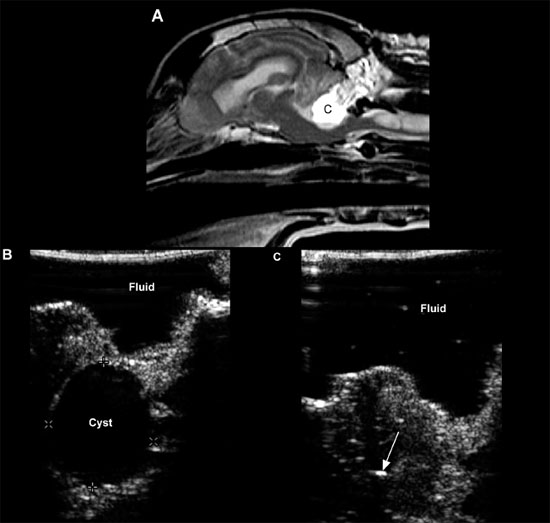

Cystic lesions can be produced by infectious disease or neoplasia or may have no apparent cause (Cruz et al. 2003) (Figure 1.18).

Choroid plexus cysts, intracranial arachnoid cysts, and epidermoid and dermoid cysts associated with the fourth ventricle, quadrigeminal cistern, or cerebellopontine angle have been reported. Arachnoid cysts are seen most commonly in the quadrigeminal cistern, where they appear as a well-defined anechoic mass between the caudal aspect of the cerebral hemispheres. The midbrain will be found ventral to the cyst, and the cerebellum will be caudal (Saito et al. 2001). Congenital cysts secondary to abnormal development or destruction of brain parenchyma, such as in Dandy-Walker syndrome and porencephaly or hydranencephaly, can also occur. Hydranencephaly is diagnosed when the cerebral hemispheres are absent or almost completely absent (Cruz et al. 2003).

Figure 1.18. Cyst in the cerebellum of an 8-year-old terrier. The cyst was drained surgically, but an astrocytoma was later diagnosed at the site (as seen in Figure 1.13). A and B: Sagittal and dorsal postcontrast T1-weighted images of the brain on which a well-defined, hypointense cystlike lesion is identified (*). C: Transverse sonogram of the cerebellum imaged from the foramen magnum on which the cyst appears as a well-defined, oval, anechoic lesion (*). D: Longitudinal sonogram of the cyst. The bone of the skull and vertebral column prevents visualization of portions of the brain and spine, but the part of the brain (arrowheads) can be seen through the foramen magnum. A portion of the spinal cord (SC) can also be observed as it joins the medulla oblongata (M) rostrally. Cursors have been placed to measure the cyst in the cerebellum. Images courtesy of D. Penninck and S. Hecht. E and F: Sonograms of a 1-year-old Chihuahua with hydrocephalus and a quadrigeminal cyst. E: Sagittal sonogram showing the quadrigeminal cyst (Q) and confluence of the dilated lateral ventricles (LV). F: Transverse sonogram. LLV, left lateral ventricle; M, midbrain; and RLV, right lateral ventricle. Images courtesy of B. Poteet, Gulf Coast Veterinary Specialists, Houston.